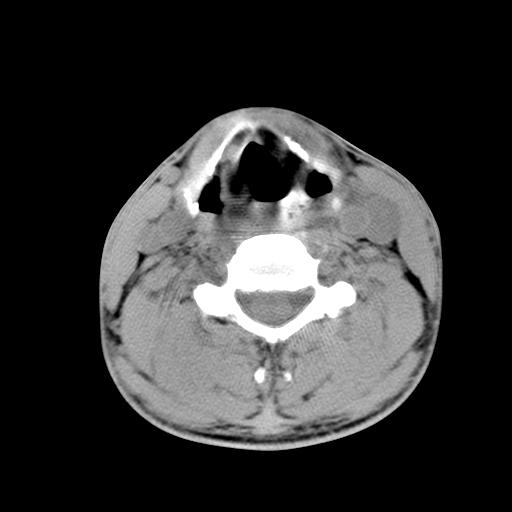

标题: CT15118:f-27y,左颈部肿一个月,无发热、无压痛 [打印本页]

标题: CT15118:f-27y,左颈部肿一个月,无发热、无压痛

1、甲状腺左叶病变:腺瘤?结节性增生?其他?

2、上极周围间隙病变。

3、2者关系?

左侧甲状腺肿大,密度不均.同侧甲状软骨似有破坏(建议传骨窗).左侧颈静脉增粗,各组织之间分界不清,有多个肿大淋巴结.甲状腺肿并感染?临床症状不符.淋巴结核?请结合其他检查.